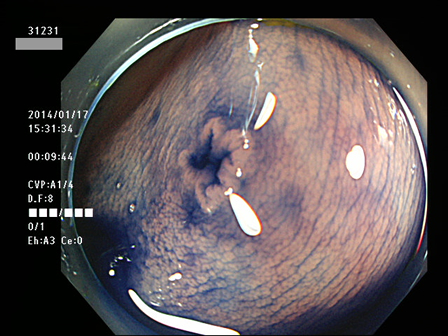

上記100名より抽出した平坦・陥凹型腺腫(=癌化の危険が高いが見落としやすい病変)の内視鏡写真

腺腫発見率 60% (カルテ番号31200〜31299の100名の方の検査結果で集計)

以下のカルテ番号の方に腺腫(Adenoma,Group3〜5)が見つかりました

31220 31222 31223 31224 31225 31229 31230 31231 31233 31234 31238 31240